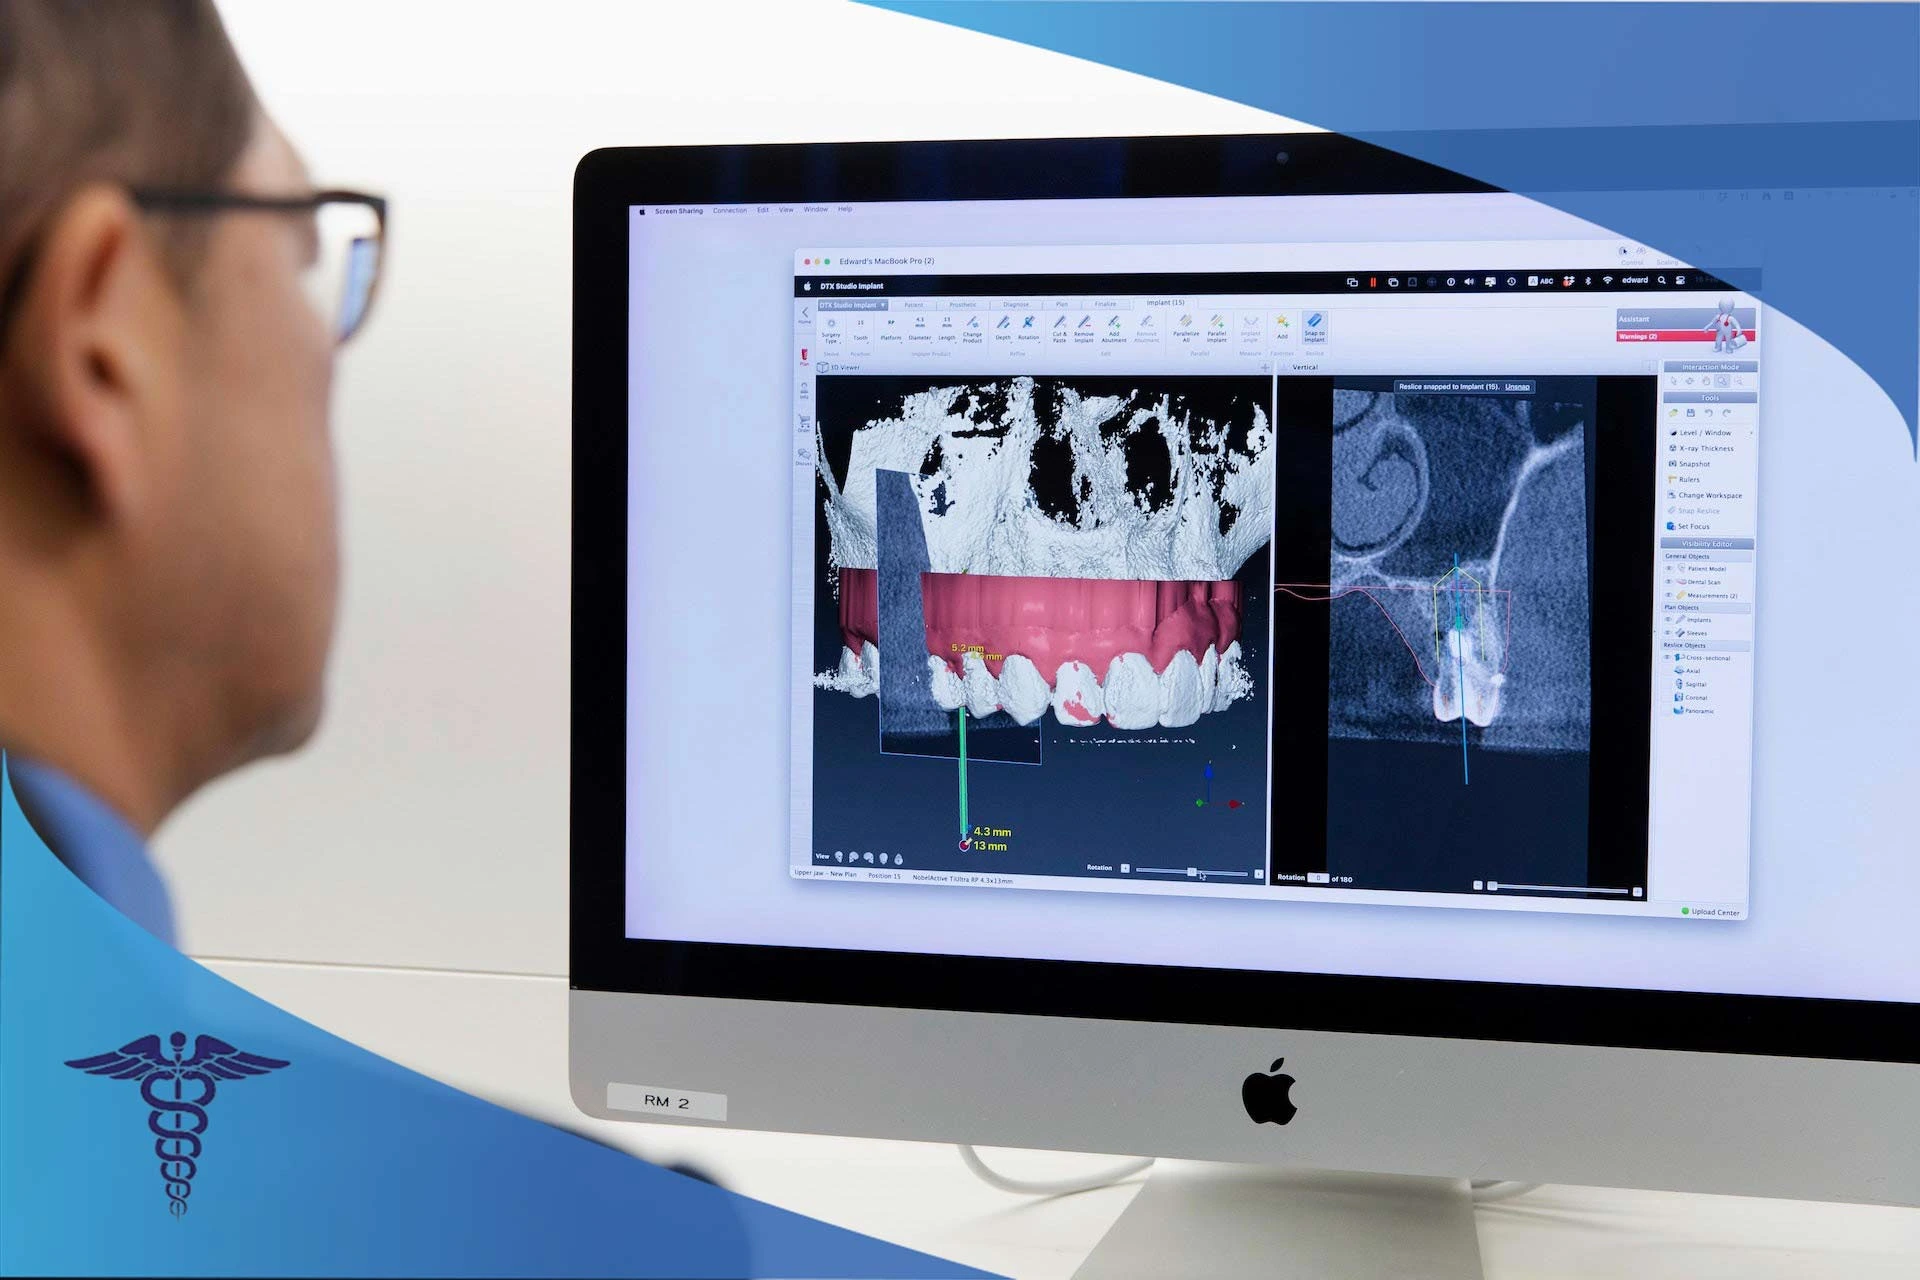

تا به حال به این فکر کرده اید که چه میشد اگر قالب گیری دندان ها برای کاشت ایمپلنت با روش های جدید انجام می شد؟ برای مثال تصویری از دهان گرفته می شد که در آن محل دقیق کاشت ایمپلنت مشخص و بدون هیچ گونه خطا و مشکلی، ایمپلنت در دهان قرار داده می شد. ایمپلنت دندان دیجیتال یکی از بهترین و جدیدترین روشهای کاشت دندان در سراسر جهان است. در حال حاضر از انواع دستگاهها و فناوریهای جدید برای این نوع ایمپلنت استفاده میشود. این روش، راهکاری جدید و آسان برای کاشت ایمپلنت در حداقل زمان و بیشترین دقت و کارایی است.

برای کاشت ایمپلنت دیجیتال در شیراز حتما باید به دندانپزشکان یا مراکزی مراجعه کنید تا تجهیزات مناسب کاشت ایمپلنت دیجیتال هستند. تجهیزاتی همچون اسکنرهای سه بعدی، نرم افزارهای اختصاصی برای تحلیل وضعیت فک و دهان و تجهیزات به روز برای ساخت روکش بر اساس تصاویر سه بعدی. در این متن از دکتر 115 قصد داریم بهترین دندانپزشکان و مراکز ایمپلنت دیجیتال در شیراز را به همراه آدرس، شماره تلفن، لینک اینستاگرام و لوکیشن معرفی کنیم. همچنین اگر قصد کاشت ایمپلنت دیجیتال شیراز را دارید، در ادامه مقاله همراه ما باشید تا بیشتر با این نوع ایمپلنت و نحوه کاشت آن آشنا شوید.

برای کاشت ایمپلنت دیجیتال در شیراز ضروری است که به بهترین دندانپزشک و مراکز تخصصی این کار مراجعه کنید. در مرحله اول ایمپلنت دندان دیجیتال، تصاویر رادیولوژی بیمار یا CBCT به طور کامل بررسی میشوند. در مرحله بعد، اسکن دهانی یا به عبارت دیگر قالبگیری از دندانها به طور کامل انجام میشود. دندانپزشک با تجهیزات اسکن می تواند کنترل بهتری روی سلامت دندان ها داشته باشد. بیایید دقیقتر با گام به گام کاشت ایمپلنت دیجیتالی در شیراز آشنا شویم.

اولین گام مهم برای درمان ایمپلنت، ارزیابی کامل دندان های شماست. برای این کار عکس های سه بعدی با کمک اسکنر CBCT از داخل دهان گرفته می شود. این تصویر نشان می دهد که استخوان کافی برای قرار دادن ایمپلنت وجود دارد یا خیر. در صورتی که وجود نداشته باشد، باید درمان پیوند استخوان و حتی لیفت سینوس برای قوس بالایی را انجام داد تا فضای بیشتری برای دسترسی به استخوان وجود داشته باشد.

مرحله چهارم: قالبگیری دیجیتال 🖥️

پس از جوش خوردن موفقیتآمیز ایمپلنتها به استخوان، ایمپلنتها باید با دندان از دست رفته شما جایگزین شود. با استفاده از اسکنر داخل دهانی سه بعدی، شکل دهان و پایه های ایمپلنت اسکن می شود. این اسکنهای دیجیتال به آزمایشگاه دندانپزشکی ارسال می شوند.

اسکن CBCT (توموگرافی کامپیوتری با پرتو مخروطی): این دستگاه به دندانپزشک اجازه میدهد تا تصویری سهبعدی و دقیق از استخوان، فک، دندانها و بافتهای نرم اطراف آن به دست آورد.

نرمافزار طراحی و شبیهسازی: مدلهای CBCT به دندانپزشک کمک میکنند تا با استفاده از تصاویر، یک مدل سهبعدی از فک بیمار ایجاد کند که این کار توسط این نرم افزارها انجام می شود.